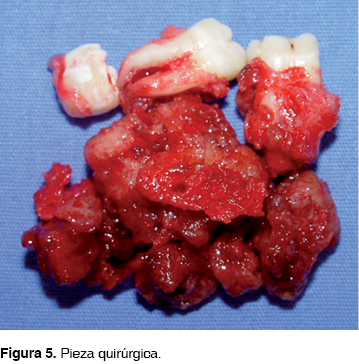

Microscópicamente la lesión se observaba con bordes bien delimitados, superficie rugosa, consistencia firme, color amarillo pálido, produciendo expansión lingual y vestibular, con dimensiones de 40 x 30 x 25 mm (Figura 5).